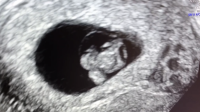

Hva tror dere ? Innvendig ultralyd

Her er ultralydene i uke 6 og 8 uenige

Uke 6 ser det ut som morkaka er mest mot venstre side og uke 8 er den på høyre side. Begge er tatt innvendig, men forskjellig ul apparat

Kort fortalt er det gjort en stor studie på 5000 tidlig ultralyder om at jentefoster fester seg på venstre side (morkake på venstre side) og omvendt for guttefoster (når man tar vaginal ultralyd.. om man tar utvendig ultralyd er sidene byttet om såklart) skal visst være 97 % sikkert. Prøv å Google det![]()